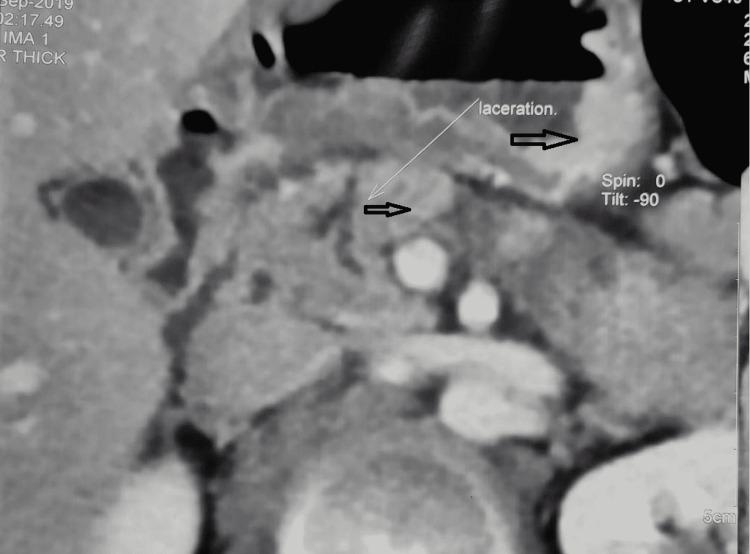

Introduction Pancreatic trauma is rare and is usually associated with adjacent organ and vascular injuries, which adds to the high morbidity and mortality. In the American Association for the Surgery of Trauma (AAST) pancreatic trauma (PT) grading system, the higher grades are a composite of less and more severe extents of injuries. We hereby present an observational study of PT with management based on an indigenous algorithmic approach. Our protocol incorporating both the extent of disruption of the main pancreatic duct (MPD) and its amenability to interventions (endoscopic, radiological, or surgical) is pragmatic. Methods Ours is a retrospective observational study of 28 consecutive cases of PT, done over a three-year period in an academic institution, by an expert Surgical Gastroenterology unit. All patients diagnosed with PT on a contrast abdominal CT scan were included. After stabilization, they were stratified and managed according to an indigenous protocol. The primary outcome measure was treatment success in terms of recovery. The secondary outcome measure was morbidity of any form. Results One patient with Grade 1 PT was operated on for associated hollow viscus injury. Two patients with AAST Grade 2 and two patients with AAST Grade 3 injury were managed successfully without surgery. Twelve of 21 patients with Grade 3 PT underwent Kimura's splenic vessel preserving distal pancreatectomy. Distal pancreatectomy with splenectomy and central pancreatectomy with Roux-en-Y pancreaticojejunostomy (PJ) was done for 7/21 and 2/21 patients, respectively, with Grade 3 PT. Two with Grade 5 injury underwent trauma Whipple. The overall mortality and morbidity rates in our series were 15.7% and 64%, respectively. Conclusion The pathogenesis in PT is a dynamic process and shows temporal evolution. These patients require serial and periodical clinical and radiological monitoring, especially in those managed conservatively initially. PT can be low or high grade. Patients with isolated low-grade PT can be managed according to the standard step-up approach for acute pancreatitis. A carefully selected subgroup of patients with partial MPD disruption either in the head or body of the pancreas can be managed by endotherapy. Complete distal parenchymal transections require early surgery tailored to individual patients in the form of either splenic vessel preserving distal pancreatectomy (SPDP) or distal pancreatectomy with splenectomy (DP+S). Damage control surgery is the dictum in unstable patients with Grades 4 and 5 injuries not responding to resuscitative measures. A trauma Whipple can be done in a carefully selected subgroup of stable patients with proximal massive disruptions in an experienced hepato-pancreatico-biliary (HPB) unit.

我们对一家学术机构的外科胃肠病学专家小组在三年期间连续收治的28例PT患者进行了回顾性观察研究。纳入所有经腹部增强CT扫描诊断为PT的患者。病情稳定后,根据本土方案对他们进行分层管理。主要结局指标是康复方面的治疗成功率。次要结局指标是任何形式的发病率。